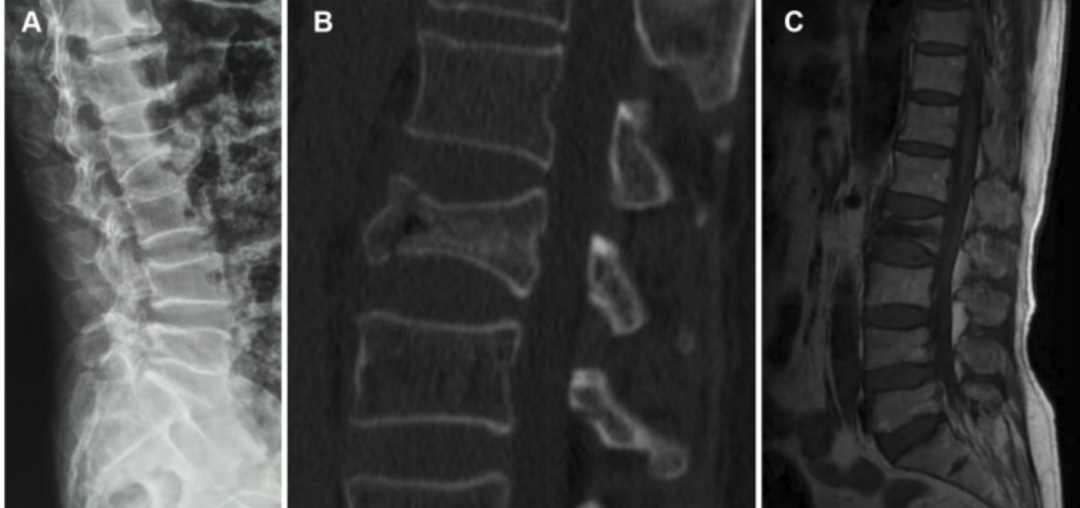

脊柱压缩性骨折,胸腰椎多见,骨折主要发生在胸或腰椎移行处,以 T12最多见,其次为L1。上位胸椎也可发生,颈椎骨折几乎没有。

(1)基于椎体形态改变将OVCFs分为3型:椎体压缩呈楔形骨折、双凹骨折和垂直压缩性骨折,

A.椎体楔形骨折:椎体前方高度变小,后方高度不变;

B.双凹状骨折:椎体前方,后方高度不变,中间高度变小;

C.压缩性骨折:椎体各部分高度均变小。其中最常见的是楔形压缩骨折(51%),常导致患者腰背痛、脊柱后凸畸形、呼吸功能降低等一系列并发症。

(2)根据Genant等将X线分型标准OVCFs分为:

A.轻度压缩骨折:在原椎体高度上压缩20%-25%。

B.中度压缩骨折:在原椎体高度上压缩25%-40%。

C.重度压缩骨折:在原椎体高度上压缩>40%。